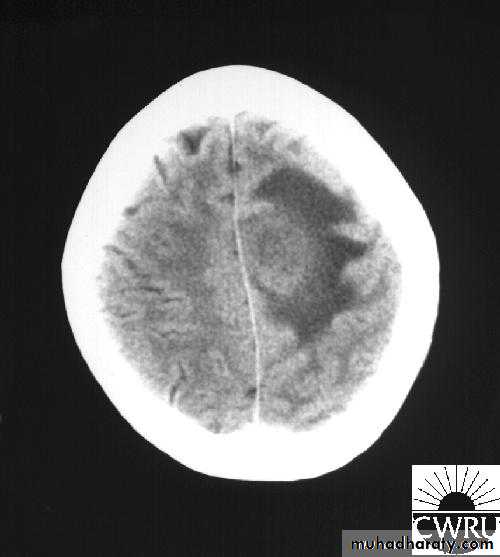

Bacterial Meningitis with suppuration

د.عبدالرحمن

Brain Abscess CT without contrast

Brain Abscess CT with contrast